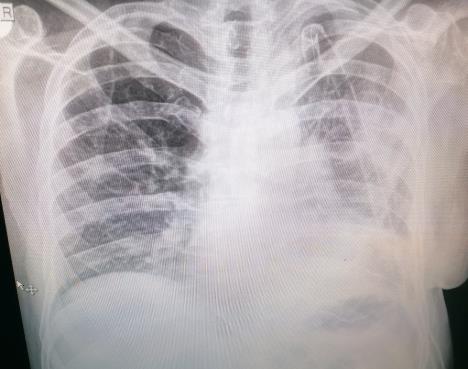

Tvit jednog srpskog lekara naišao je na burne reakcije pa i pohvale građana u kome je objasnio kako je uz pomoć jedne starinske metode izlečio pacijenta od HOBP (hronične opstruktivne bolesti pluća).

- Elem, pacijenta sam primio pred Novu godinu, zbog toga što mu je "pukla" pluća maramica levo. Čovek boluje od nelečene HOBP na koju je fasovao koronu.

LEKAR TVRDI: EKSPERIMENT USPEO! Izlečio sam zaraženog pacijenta od teške bolesti pluća uz ovu MATORU metodu! Ovo će vas iznenaditi Foto: Printscreen

Zbog terapije ogromnim količinama kortikosteroida, na takva pluća je zaradio bakterijsku super-infekciju koja je i dovela do toga da dobije dren, a onda zbog daljih komplikacija ga odvedem u salu. Iseče mu se taj deo pluća i nalaz kaže da se radi o hronično nekrotičnoj pneumoniji - trule mu pluća zbog bakterije. Postoperativno peti dan opet počne da gubi veću količinu vazduha - piše u tvitu i dodaje: